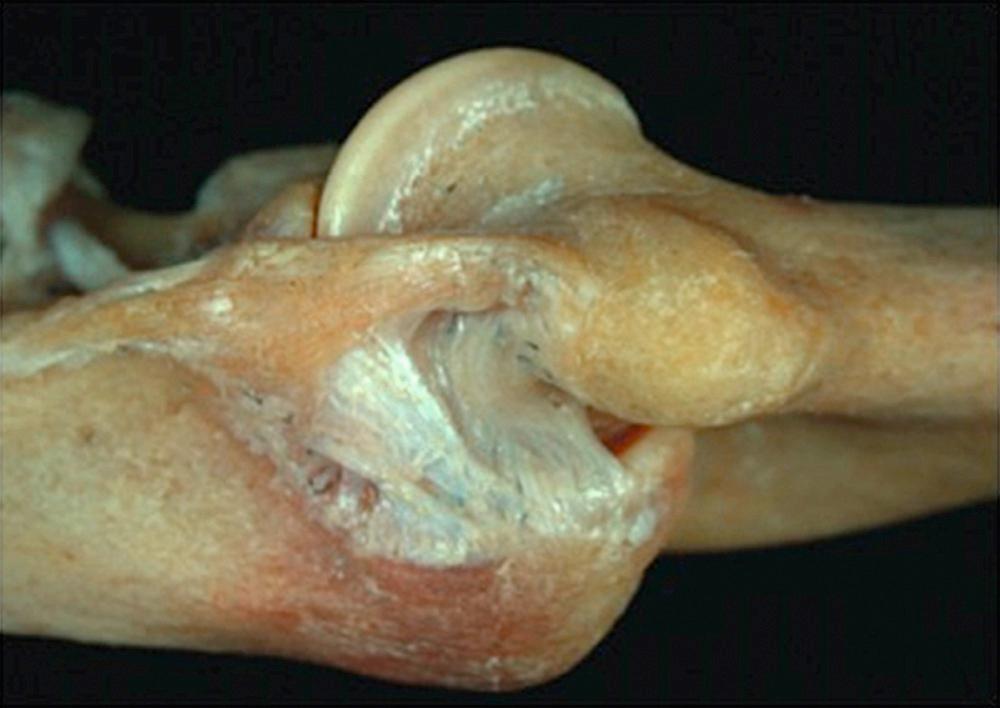

There are three major independent stabilizers of the elbow joint: the ulnohumeral joint, the anterior bundle of the medial collateral ligament, and the lateral ulnar collateral ligament ( Fig. 36.1 ). These three key elements for elbow stability alone allow for a stable, functioning elbow joint. Although the radial head is a “secondary stabilizer,” in the context of the unhappy triad, it assumes the role of a primary stabilizer.

FIG 36.1, The primary stabilizers of the elbow include both collateral ligaments, which stabilize the ulna against the trochlea.